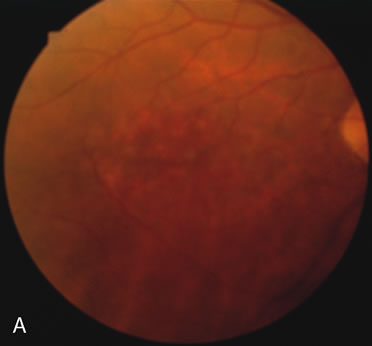

In retinitis pigmentosa (RP), the pigment abnormalities of atrophy, migration, and clumping are made apparent by transmitted hyperfluorescence and blocked hypofluorescence (Fig. 1A). Patients who have very minimal pigmentary alterations (pauci pigmentary RP) or no pigment abnormalities (RP sine pigmento) may show the abnormalities on fluorescien angiography (FA). It is uncommon to see choriocapillaris atrophy except in the late stages. This finding corresponds to the histopathology, which shows that the earliest abnormalities are in the photoreceptors and that the choroid is normal.1